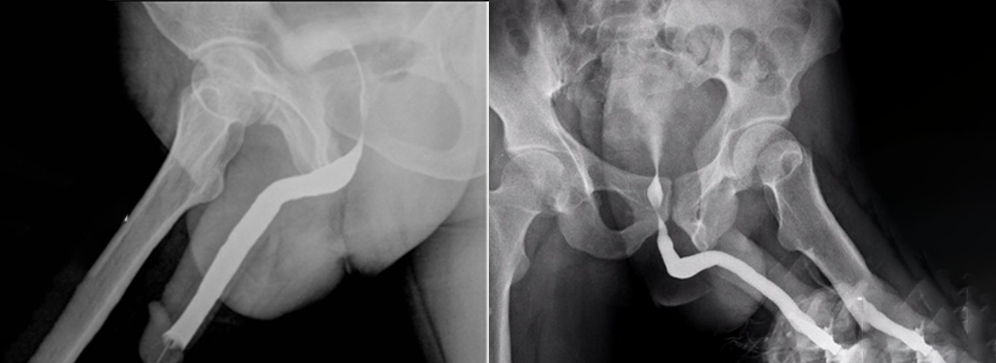

A Retrograde Urethrogram (RGU) is a specialized X-ray procedure used to examine the urethra by injecting a contrast medium into the external opening of the urethra, allowing the dye to flow backward through the tube. This backward, or “retrograde,” flow highlights the urethra on X-ray images, enabling the radiologist to observe the exact size, shape, and any abnormalities such as narrowing (strictures), tears, or fistulas. It is particularly helpful in cases where patients report difficulty urinating, experience recurrent urinary tract infections, or have a history of trauma or surgery involving the urinary tract.

The Retrograde Urethrogram is performed by gently inserting a small catheter or syringe into the external opening of the urethra. A water-soluble contrast dye is slowly injected, flowing backward through the urethra while a series of X-ray images are captured. Although you may feel some pressure or mild discomfort during the injection, the procedure is usually quick and well tolerated.

For the Ascending Urethrogram, contrast medium is introduced in a way that allows it to flow naturally as you urinate, enabling dynamic imaging of the urethra under normal function. This part of the procedure often requires cooperation in following instructions for timing urination during imaging. Our highly trained staff explain each step clearly and monitor your comfort closely, ensuring the procedure is as smooth and stress-free as possible.